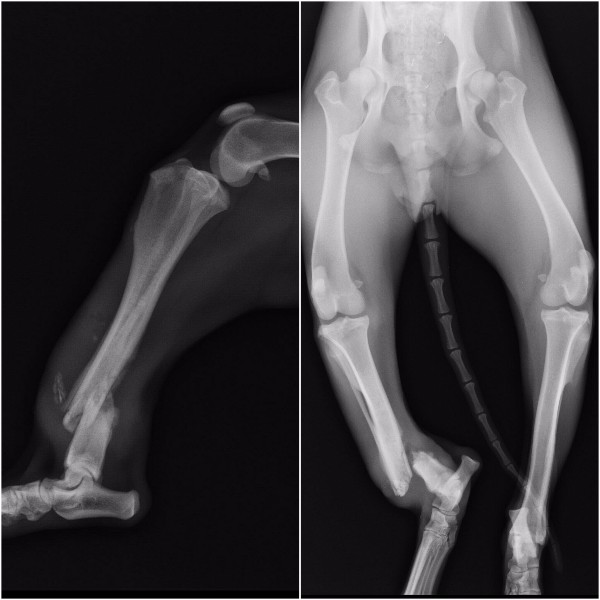

Open fractures of both right tibia and fibula. Severe tissue swelling, bone and tissue infections.

Open fractures of both right tibia and fibula. Severe tissue swelling, bone and tissue infections.

I rushed her to Veterinary Care Specialists in Milford. She had an open fracture (bone sticking out) of her tibia and fibula on her right rear leg from being hit by a car. She also has road rash all over but that will mend over time. I got a 2nd opinion at Towne and Country Vet and a 3rd opinion at Animal Surgical Center of MI in Flint.

It was ultimately determined she had been hit by a car weeks ago and she already had severe infection in her bones and surrounding tissues. If we would have tried an external fixture to try and save her leg she had a very high chance of failure and needing an amputation anyways.

I rushed her to Veterinary Care Specialists in Milford. She had an open fracture (bone sticking out) of her tibia and fibula on her right rear leg from being hit by a car. She also has road rash all over but that will mend over time. I got a 2nd opinion at Towne and Country Vet and a 3rd opinion at Animal Surgical Center of MI in Flint.

It was ultimately determined she had been hit by a car weeks ago and she already had severe infection in her bones and surrounding tissues. If we would have tried an external fixture to try and save her leg she had a very high chance of failure and needing an amputation anyways.